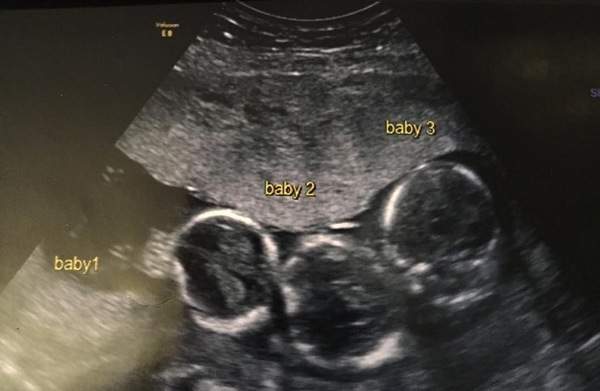

Early in her pregnancy, Becki-Jo experienced severe sickness and headaches. Because of this, her doctors scheduled an ultrasound a little earlier than usual — which is how they discovered she was expecting triplets.

The three boys — Rohan, Roman, and Rocco — were born via Cesarean section at 31 weeks, each weighing about 3 pounds 5 ounces. They spent their first six weeks in intensive care, building strength until they were ready to thrive on their own.